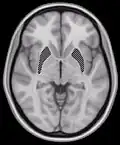

Horizontal slice of MRI-image showing the putamen. The other nuclei of the basal ganglia (caudate nucleus and globus pallidus) can be seen as well.